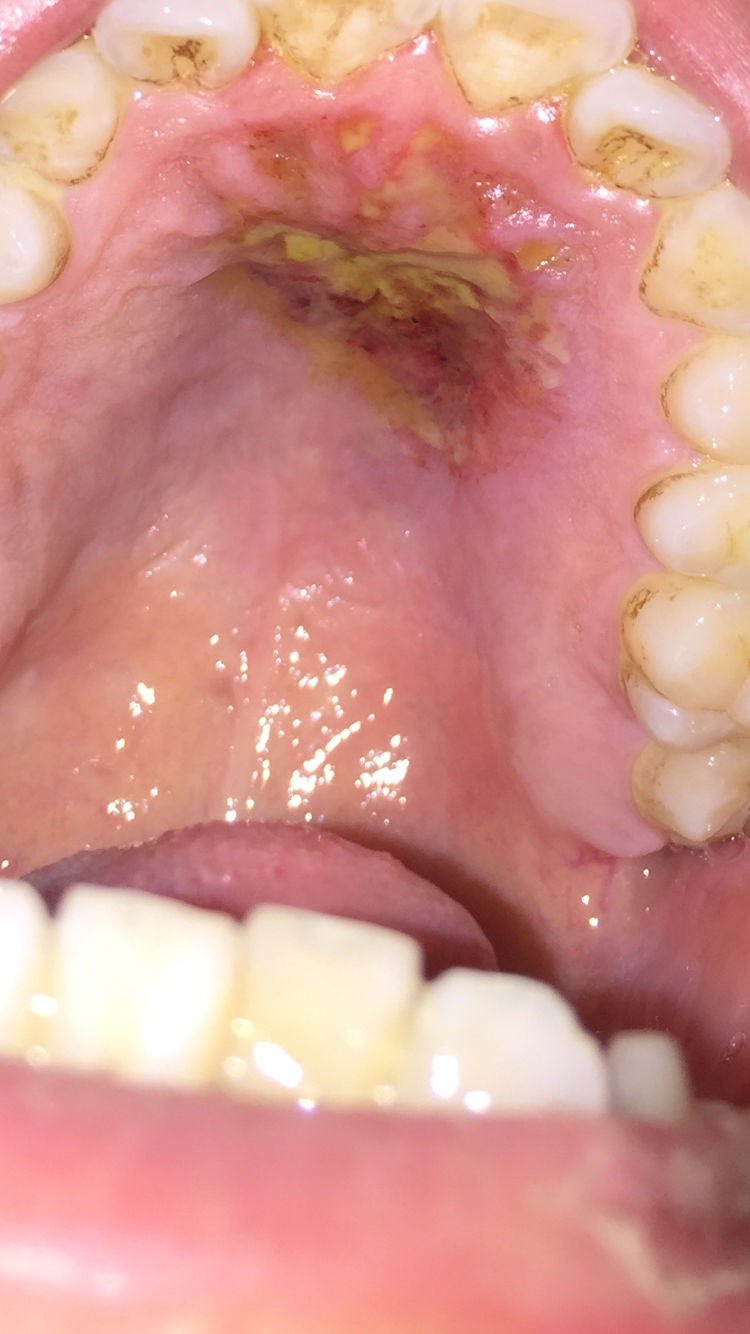

一擦就灵的口腔溃疡秘方:

图片来源于网络,如有侵权,请联系删除

地塞米松注射液一支,庆大霉素注射液一支,混合后用棉签擦创面。